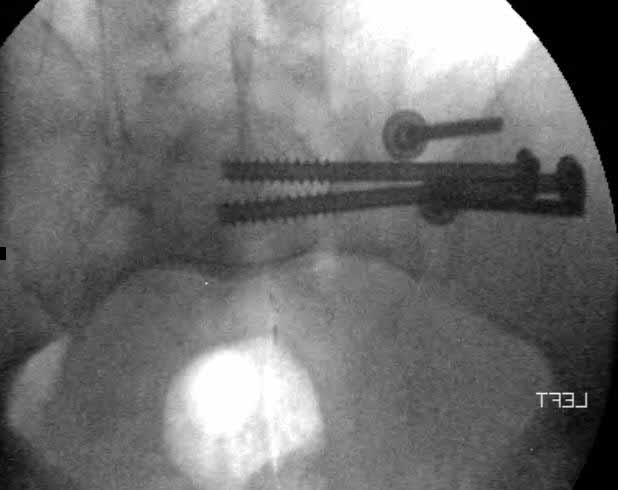

Patient was prone for procedure, as I thought too difficult to fix the wing in lateral position. Of course the repair of wing was easy, but reduction of SI very demanding. The Floro images document the residual lack of reduction. That was the closest I could get it using 6mm joystick in wing, and clamp on sacrum and clamp through notch.  The fixation was (initially) rigid. Anterior ex fix with supra-acetabular pins was placed due to condition of soft tissues, massive "beer-belly" overhanging the crest.

Post trauma day ten patient's xray shows failure of posterior construct. Plan was to perform revision orif once soft tissues resolve considerably for full anrterior fixation and posterior fixation. However, while Im away for holiday (on Post trauma day 15), pt is developing septic clinical appearance, and trauma suspects pelvic abcess near symphysis and performs I and D - finds nothing but no primary closure performed. Posterior tissues/incision continue to look healthy. Now is post trauma day 17, pt is still tubed/on dopamine/and wbc still elevated, anterior incision still packed open.

5. Your caudal iliosacral screw is/was in his spinal canal...it's low and posterior and the lateral fluoro image confirms this...a postop CT will show it (or it's trail at this point)...canal screws do not hold.